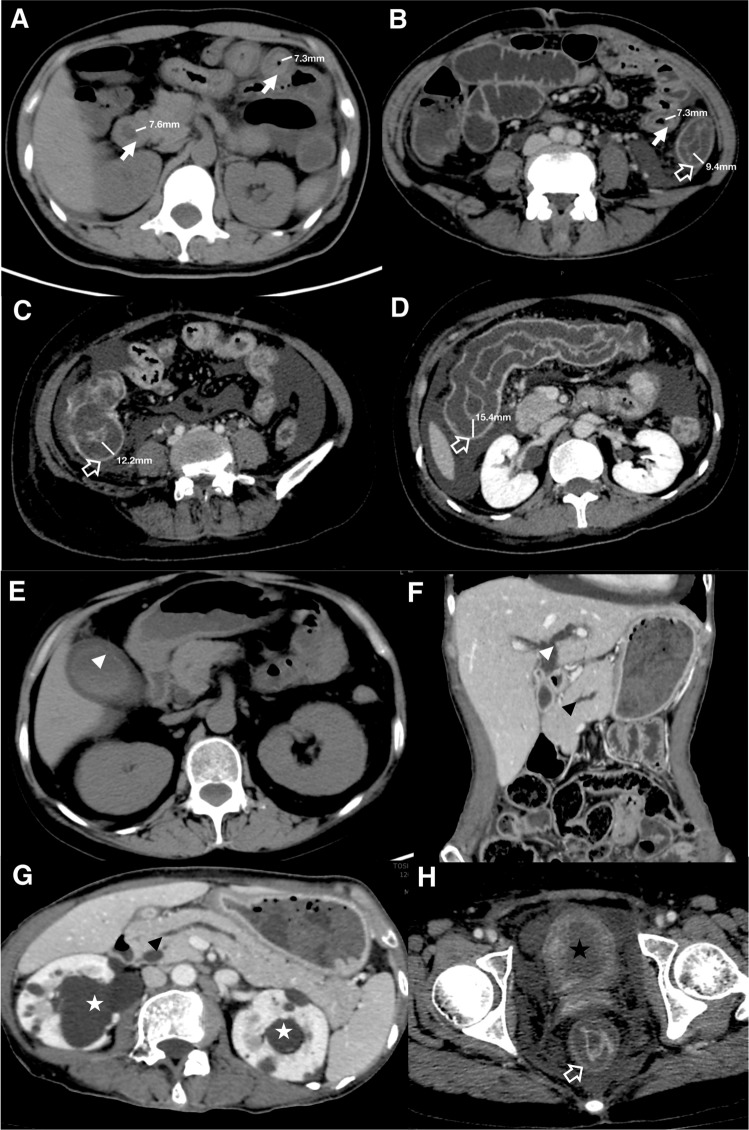

Figure 2.

Illustrations of CT scoring. Representative images from 4 patients to illustrate CT scoring process (A–H). “White arrow” refers to small intestine (duodenum and jejunum, A; ileum, B). “White hollow arrow” refers to large intestine (descending colon, B; ileocecum, C; transverse colon, D; rectum, H). Measurements of the thickness of bowel walls are indicated by white bars. “Arrow head” refers to pancreatico-biliary system involvement (white arrow head: gall bladder wall thickening, E, biliary duct dilatation, F; black arrow head: pancreatic duct dilatation, F,G). “Asterisk” refers to urinary involvement (white asterisk: ureterohydronephrosis, D,G; black asterisk: bladder wall thickening, H).